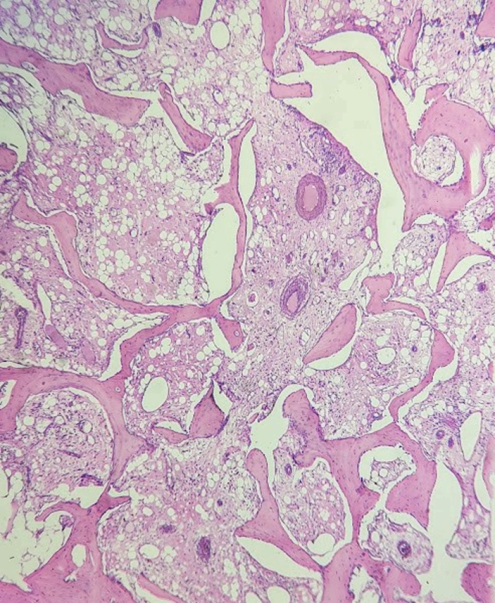

El estudio histológico evidenció osteomielitis crónica supurativa asociada a necrosis ósea. (Fig. 1 a 3)

Figura 1: Trabéculas óseas adelgazadas y espacios medulares ocupados por tejido fibroso laxo vascularizado.